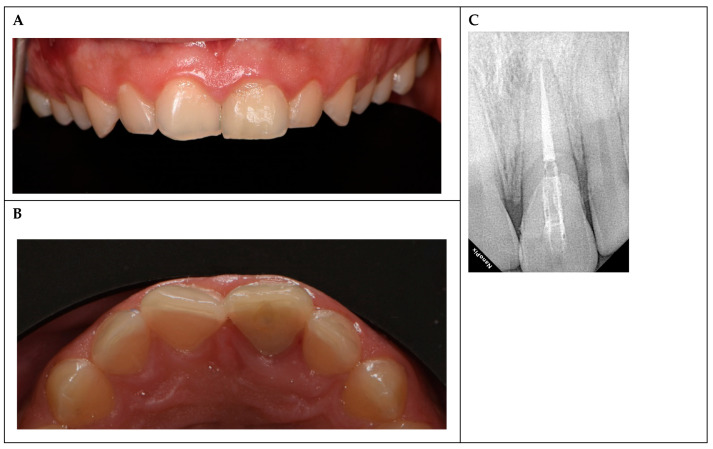

背景与临床意义:外伤性牙损伤,尤其是复杂的恒切牙冠骨折在青少年中很常见,上颌中切牙因其位置突出而最常受影响。这些损伤通常是由运动或意外造成的,需要及时处理,以防止髓质坏死或感染等并发症,这些并发症会影响长期预后。当骨折节段完整时,碎片再附着提供了一种保守、美观的方法,其结果与复合修复相当。本病例报告强调了及时干预和先进的修复技术在儿科牙科的重要性。病例介绍:一名16岁的男性在足球比赛中表现出左上中门牙复杂的冠状骨折。骨折向龈下延伸,牙髓暴露。病人用生理盐水保存碎片。治疗包括使用牙本质粘接剂和可流动复合树脂重新附着碎片,随后由于延迟出现(48小时)而进行单次根管治疗。由于严重的冠状损失,放置了玻璃纤维桩来加强修复。随访3年(1、3、6、12、24和36个月),无临床或影像学并发症,牙齿无症状,功能正常。结论:本病例强调了结合细致的技术和长期监测碎片再附着的有效性。

Background and Clinical Significance: Traumatic dental injuries, particularly complicated crown fractures of permanent incisors, are common in adolescents, with maxillary central incisors most frequently affected due to their prominent position. These injuries, often resulting from sports or accidents, require prompt management to prevent complications such as pulp necrosis or infection, which can compromise long-term prognosis. Fragment reattachment offers a conservative, esthetically favorable approach when the fractured segment is intact, with outcomes comparable to composite restorations. This case report underscores the importance of timely intervention and advanced restorative techniques in pediatric dentistry. Case Presentation: A 16-year-old male presented with a complicated crown fracture of the upper left central incisor sustained during a soccer game. The fracture extended subgingivally with pulp exposure. The patient preserved the fragment in saline. Treatment involved fragment reattachment using a dentin bonding agent and flowable composite resin, followed by single-visit root canal therapy due to delayed presentation (48 h). A glass fiber post was placed to reinforce the restoration due to significant coronal loss. Three years of follow-up visits (1, 3, 6, 12, 24, and 36 months) revealed no clinical or radiographic complications, with the tooth remaining asymptomatic and functional. Conclusions: This case underscores the effectiveness of fragment reattachment when combined with meticulous technique and long-term monitoring.